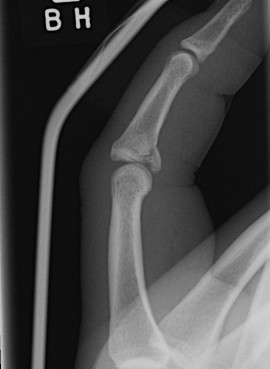

Dorsal Blocking K wire

Technique

- flexion P2

- dorsal entry into P1

- 40o flexion

- early removal at 3/52

- Improvement compared to extension blocking